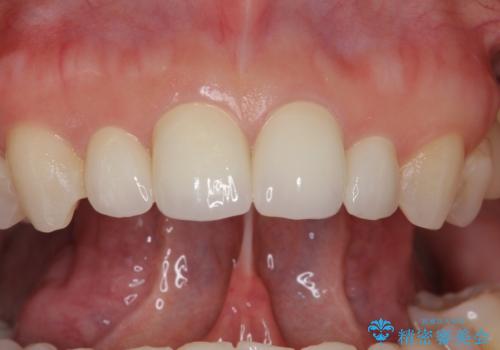

隣の前歯が小さいため、4本被せてバランスをとりました。

4本セラミックにすると大きさだけでなく、色も揃えられるのでおすすめです。

- ジルコニアクラウン(スタンダード) 11万円×4本、仮歯 1万円×4本費用は治療当時の料金となります